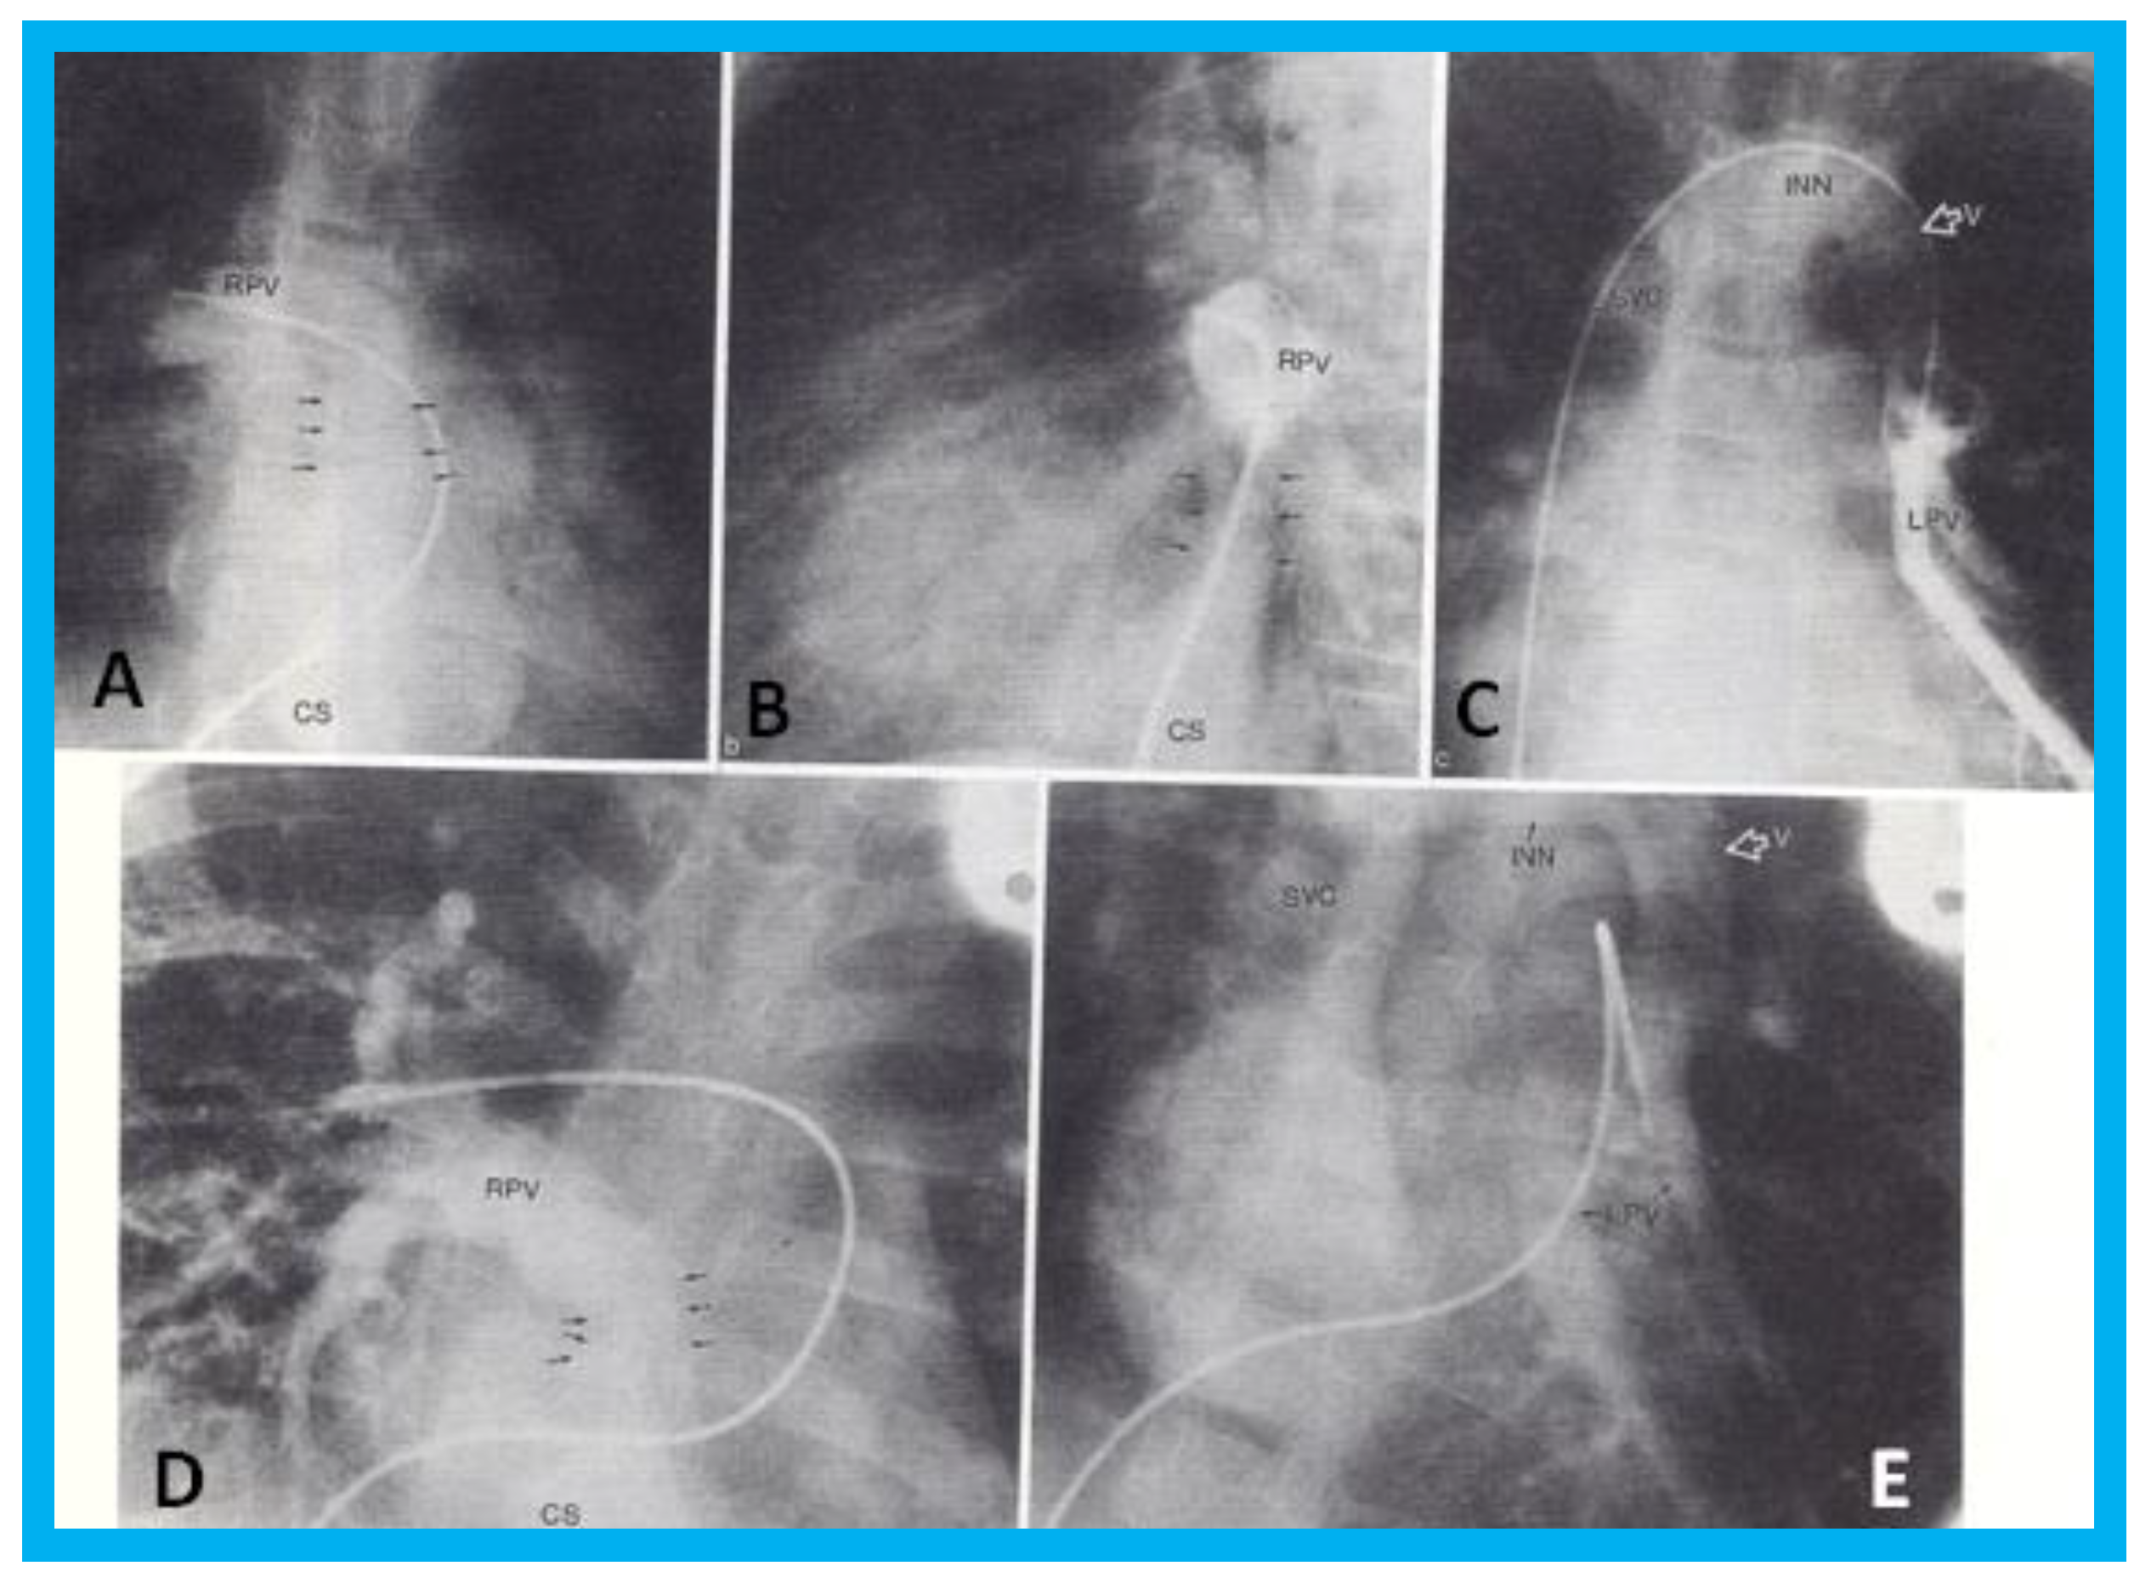

Transthoracic echocardiogram in case 1 showed dilated right atrium (RA) and right ventricle (RV) with a common pulmonary venous confluence (Figure 6a) and a vertical vein emptying into the innominate vein and superior vena cava (SVC) (Figure 6b,c). Dilated coronary sinus (CS) with mosaic color-Doppler flow pattern of pulmonary venous entry was also seen (Figure 6d,e). These findings indicated mixed type of total anomalous pulmonary venous connection. The findings in case 2 were very similar to those seen in case 1. However, not all pulmonary veins were identified and their course and connections to the pulmonary venous confluence could not be established. Therefore, catheterization and cineangiography were undertaken to validate the diagnosis prior to corrective cardiac surgery. Levo-angiographic frames following right pulmonary artery cineangiogram demonstrated entry of right pulmonary veins into the coronary sinus in both cases (Figure 7a,b,d). Direct injection into the left pulmonary vein via a catheter positioned into it via the innominate and vertical veins in the first case (Figure 7c) and on levo-angiogram following left pulmonary artery cineangiogram in the second case (Figure 7e) clearly demonstrated left pulmonary venous drainage via the vertical vein into the systemic venous circuit. Transesophageal echocardiography during surgery in both cases could not delineate the number of pulmonary veins and their connection with the confluence, although we had only access to single-plane TEE probe at that time.

On the basis of the experience in these two cases, we recommended angiographic definition of all pulmonary veins in mixed type of TAPVC at that time [8]. With today’s availability of better echocardiography machines (compared with mid-1990s) and multi-plane transesophageal probes, angiography may not be needed in most patients suspected of having mixed type of TAPVC. Certainly, today’s cross-sectional imaging can define the anatomy in most patients with mixed TAPVC and angiography may not be necessary.

Figure 7. Selected cineangiographic frames from postero-anterior (A,D,E) and lateral (B,C) views of case 1 (AC) and case 2 (D,E) demonstrating mixed total anomalous pulmonary venous connection. In (A,B), levo-angiographic frames following right pulmonary artery cineangiogram demonstrated entry of right pulmonary vein (RPV) into the coronary sinus (CS) in case 1. In (C) is the selected angiographic frame from left pulmonary vein (LPV) cineangiogram demonstrating pulmonary venous drainage into the vertical vein (V) and then into the innominate vein (INN) and superior vena cava (SVC), also of case 1. In (D), levo-angiographic frame following right pulmonary artery cineangiogram demonstrating entry of right pulmonary vein (RPV) into the coronary sinus (CS) in case 2 is shown. In (E), levo-angiographic frame following left pulmonary artery cineangiogram demonstrating drainage of left pulmonary veins (LPV) into the vertical vein (V) and then into the INN and SVC of case 2 is shown. In (A,B,D), the connections of the RPVs to the CS are marked with arrows to improve clarity. Reproduced from Reddy S.C.B., et al. [9].